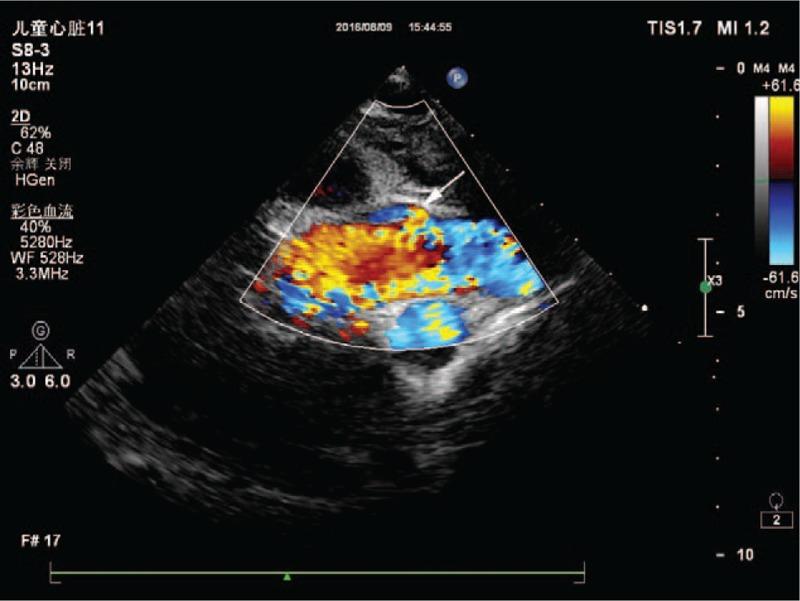

The preoperative echocardiogram confirmed the presence of an atrial septal defect, and during the surgical procedure, a high take-off right coronary artery was found.

Postoperative echocardiogram verified the presence of the high take-off right coronary artery and a satisfactory repair of the atrial septal defect. The postoperative course was uneventful, and the patient was discharged on postoperative day 5.

术前超声心动图证实存在房间隔缺损,手术过程中发现右冠状动脉高位起始。

结果